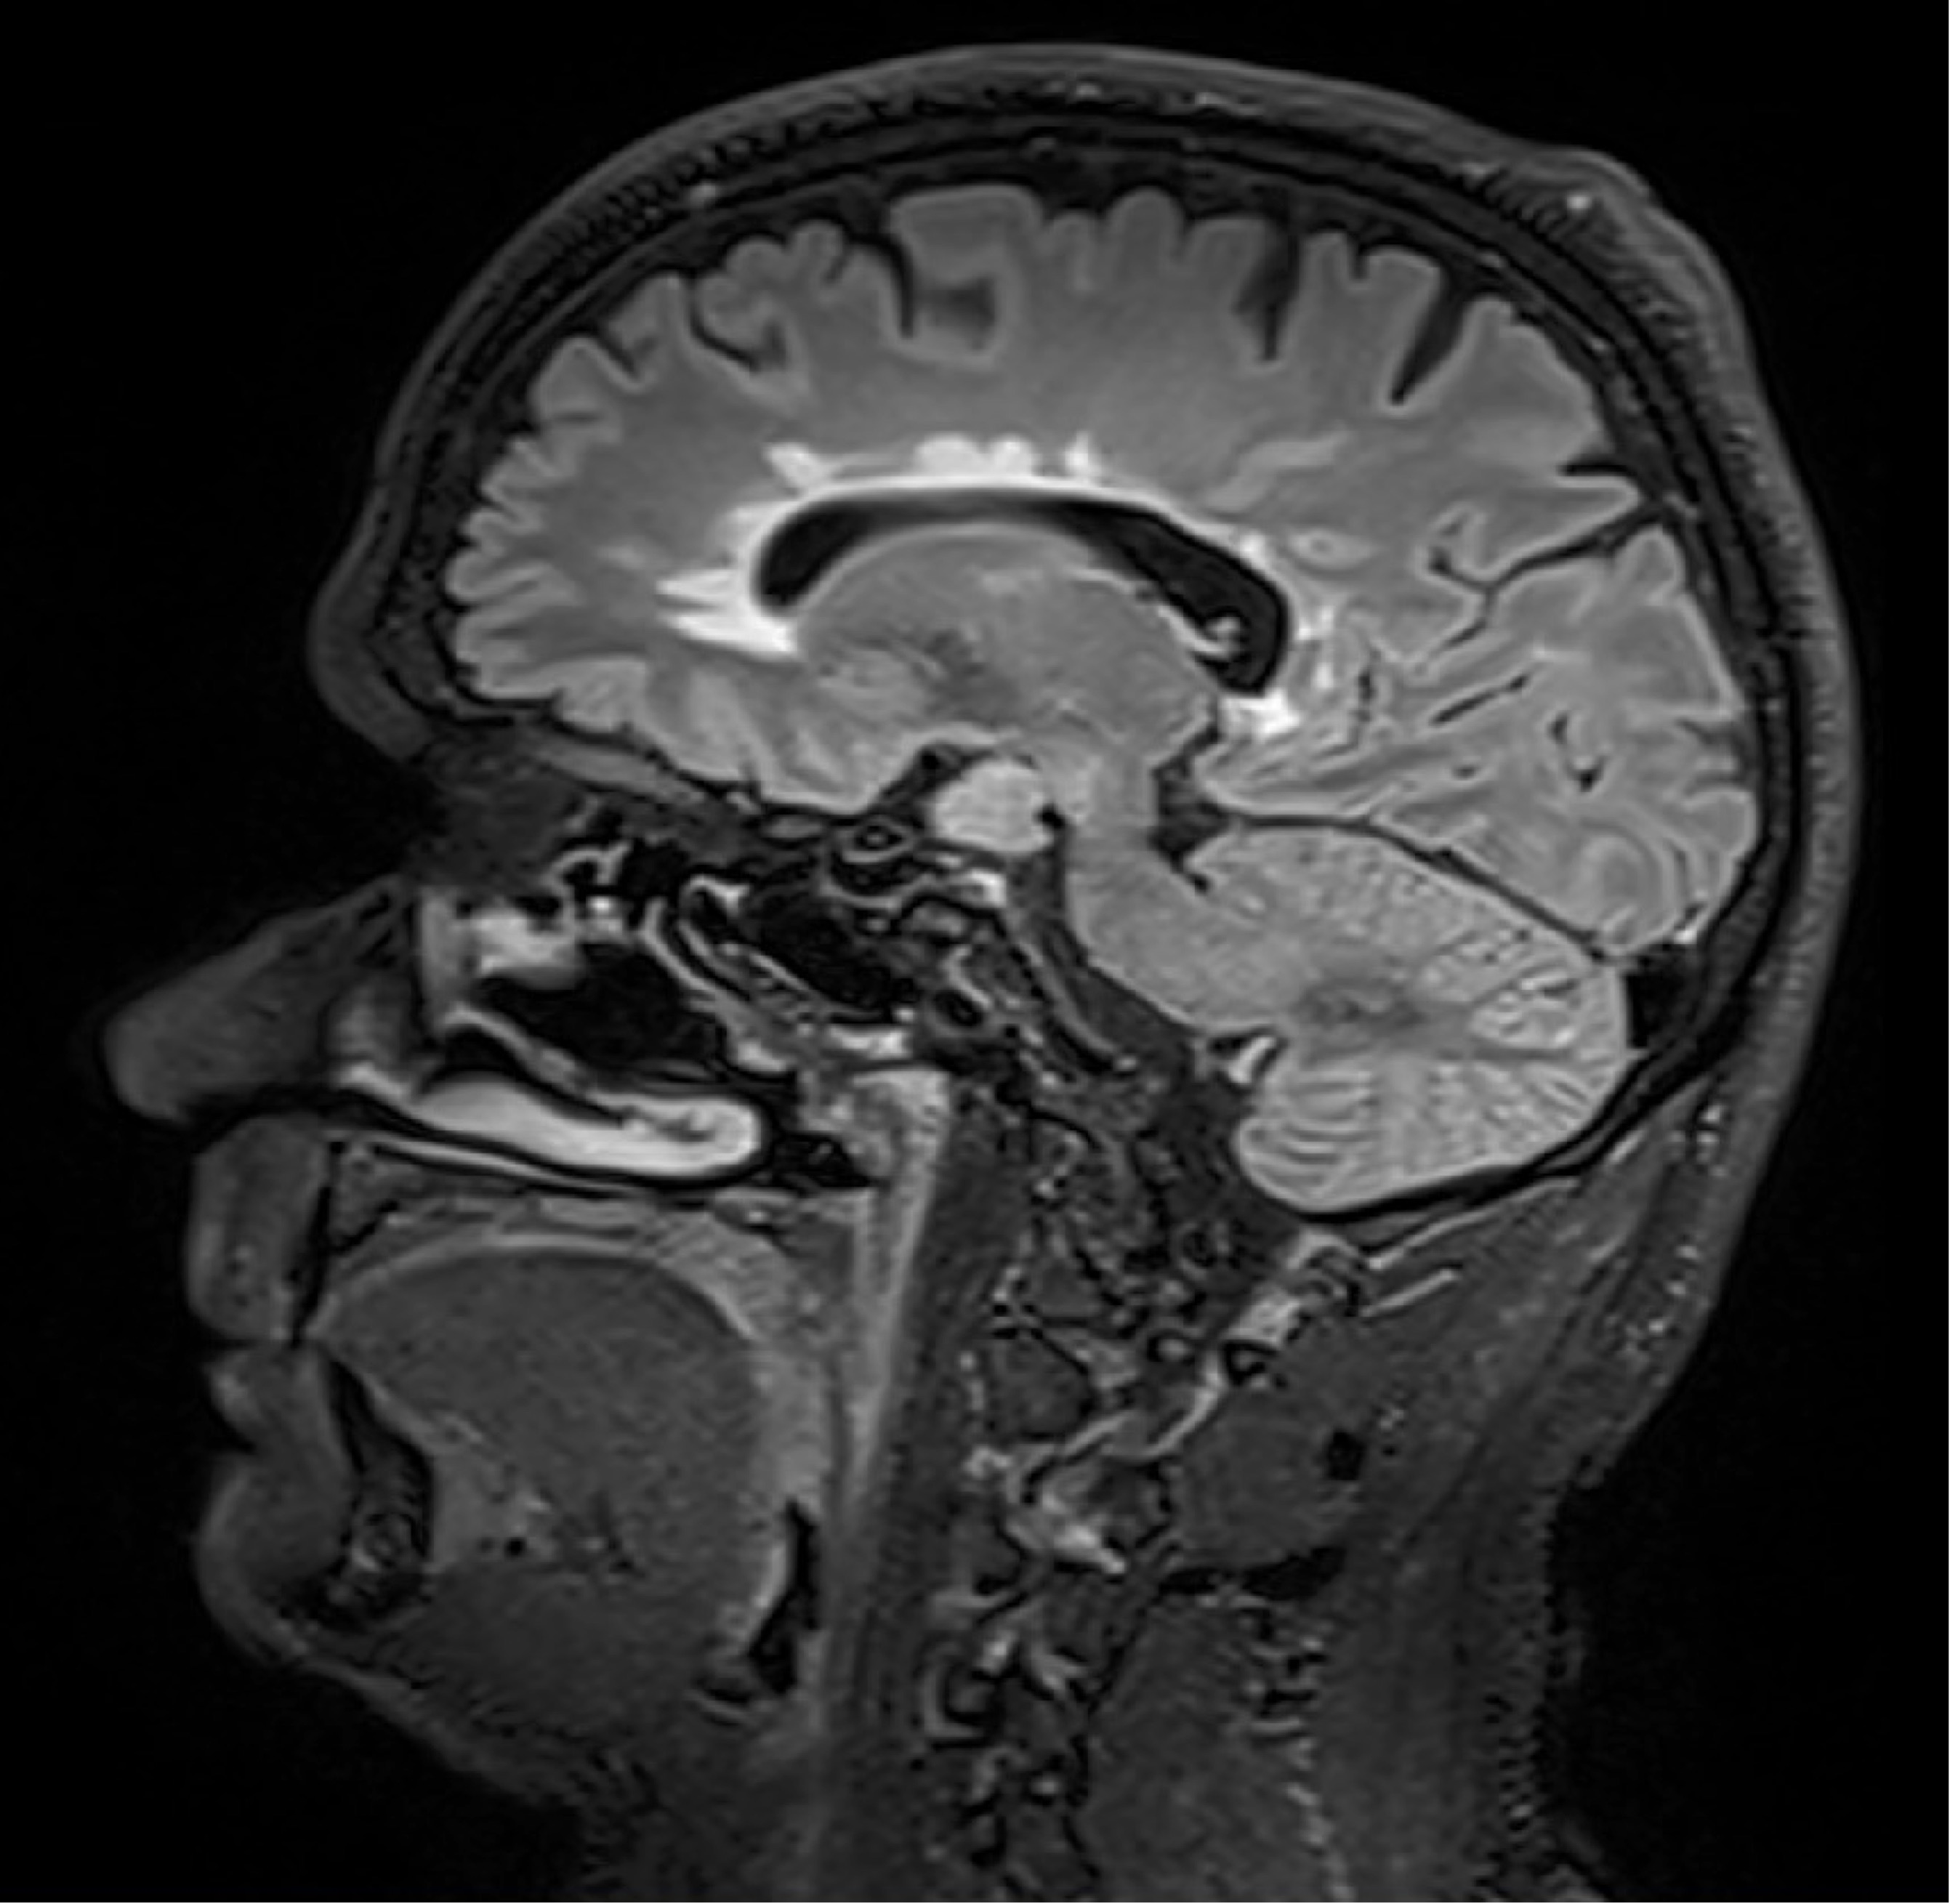

Abseits klinischer Symptome, die von Einschränkungen des Sehvermögens bis hin zu Lähmungserscheinungen ein breites Spektrum umfassen, kann die Krankheitsaktivität bei MS auch bildgebend dargestellt werden. „Der Nachweis entzündlicher Läsionen im Gehirn mittels MRT erlaubt auch eine Einschätzung geringerer Krankheitsaktivität, denn vermeintlich stabile Patient:innen können trotz Therapie weiterhin neue, klinisch stumme, entzündliche Veränderungen entwickeln“, weiß Neuroimmunologe Harald Hegen, der an der Innsbrucker Univ.-Klinik für Neurologie bereits seit vielen Jahren zu MS forscht.

In die Studienkohorte wurden 131 MS-Patient:innen aus MS-Zentren in Österreich und der Schweiz eingeschlossen, die unter einer gering- bis moderat-effektiven Immuntherapie zwölf Monate lang klinisch stabil waren und dann einer MRT unterzogen wurden. „Wir konnten zeigen, dass Patient:innen mit schubförmiger MS, die unter Immuntherapie zwei oder mehr neue entzündliche MRT-Läsionen innerhalb eines Jahres entwickeln, auch bei klinischer Stabilität, also ohne Symptome, von einem Wechsel auf eine hoch-effektive Immuntherapie profitieren“, beschreibt Erstautor Gabriel Bsteh von der Medizinischen Universität Wien die zentrale Erkenntnis. Damit liefert die Studie eine für den klinischen Alltag wichtige Erkenntnis, die für die individuelle Therapieanpassung genutzt werden sollte.

„Nachdem Läsionen oft schon vor dem Auftreten klinischer Symptome in der MRT sichtbar sind, ermöglicht eine bildgebende Kontrolle bei Patient:innen mit einer gering- bis moderat-effektiven Therapie ein frühes Eingreifen in den individuellen Krankheitsverlauf“, betont Studienleiter Harald Hegen. In der Studienkohorte waren rund 40 Prozent der Patient:innen klinisch stabil, zeigten allerdings in der MRT schon eine oder mehrere Läsionen. Bislang war in der klinischen Praxis eine Therapieverstärkung nur nach Auftreten klinisch manifester Symptome angezeigt.